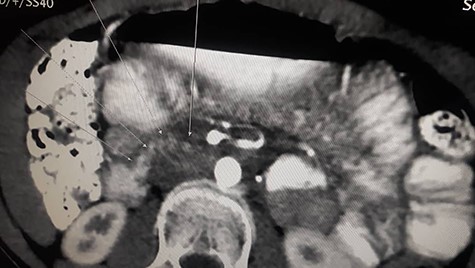

Patient underwent contrast enhanced CT scan for abdomen and pelvis, which revealed severely dilated stomach and significant dilatation of the duodenum up to the level of the distal third part, abrupt narrowing (transition zone) was seen just anterior to the AA and posterior to the SMA (Figs. 1 and 2) as well as significant reduction of the aortomesenteric angle (measuring 8.1°) and aortomesenteric distance measuring about 7 mm (Fig. 1).

Contrast enhanced CT scan abdomen and pelvis (sagittal view) (axial view) showing duodenal compression between the aorta and superior mesenteric artery.